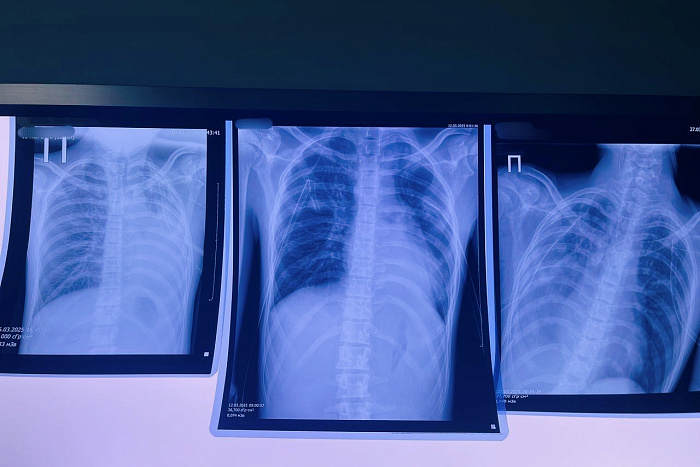

Один из последних инцидентов едва не стоил жизни 16-летнему юноше — у него произошел разрыв булл в легких, вызвавший опасное состояние — двусторонний пневмоторакс. После экстренной операции пациента пришлось перевести в федеральную клинику, где он продолжает борьбу за жизнь.

Медики отмечают тревожную тенденцию: все чаще у молодых вейперов диагностируют EVALI — особую форму поражения легких, связанную с токсичным воздействием веществ из электронных сигарет. Особую опасность представляет ацетат витамина Е, который при нагревании превращается в вязкую массу, намертво прилипающую к легочной ткани.

Хирург Виталий Лапшин предупреждает: образовавшиеся в легких воздушные пузыри могут разорваться в любой момент, что создает прямую угрозу жизни. Медики настаивают — вейпинг не является безопасной альтернативой курению и представляет особую опасность для развивающегося организма подростков.